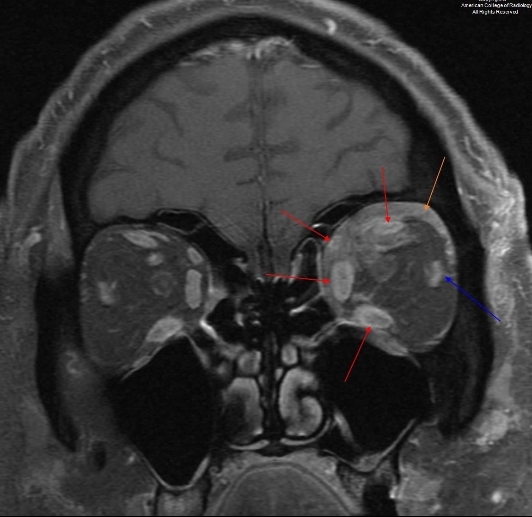

图 4 为增强 T1 压脂冠状位,示上直肌、内直肌、下直肌和上斜肌增粗且强化(红色箭头),外直肌受累不明显(蓝色箭头),并有肌锥外脂肪和眶骨膜浸润性表现(桔色箭头)